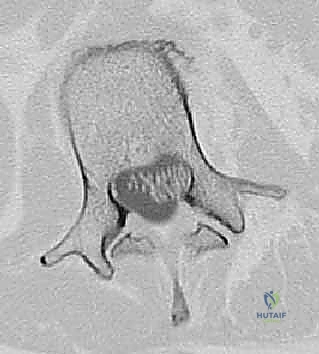

عملية دمج الفقرات (Spinal Fusion) هي إجراء جراحي يهدف إلى ربط فقرتين أو أكثر بشكل دائم، مما يزيل الحركة غير الطبيعية والمؤلمة بينهما، ويعيد الاستقرار الميكانيكي إلى العمود الفقري. في حالتنا هذه، يتم التركيز بشكل خاص على المنطقة الصدرية القطنية (Thoracolumbar Junction)، وهي المنطقة الانتقالية الحرجة التي تربط الجزء العلوي من الظهر (القفص الصدري الصلب) بالجزء السفلي (المنطقة القطنية المتحركة). يتم التثبيت باستخدام أدوات طبية معدنية متطورة (Instrumentation) مثل المسامير السويقية (Pedicle Screws) والقضبان المصنوعة من التيتانيوم.

المنطقة الصدرية القطنية (Thoracolumbar Junction): نقطة الضعف الميكانيكية

هذه المنطقة (من T11 إلى L2) تعتبر نقطة انتقال ميكانيكي حرجة. الجزء الصدري فوقها صلب ومقيد بالقفص الصدري، بينما الجزء القطني تحتها مرن ومتحرك. هذا الانتقال المفاجئ من الصلابة إلى المرونة يجعل هذه المنطقة عرضة بشكل غير متناسب للكسور الرضية (مثل كسور الانفجار بسبب حوادث السيارات أو السقوط من ارتفاع) والإجهاد الميكانيكي الذي يؤدي إلى الانزلاق الفقاري.

* التصوير المقطعي المحوسب (CT Scan): يوفر صوراً ثلاثية الأبعاد للعظام، وهو ضروري جداً للتخطيط الجراحي الدقيق وتحديد أحجام المسامير المناسبة لكل سويقة فقارية.